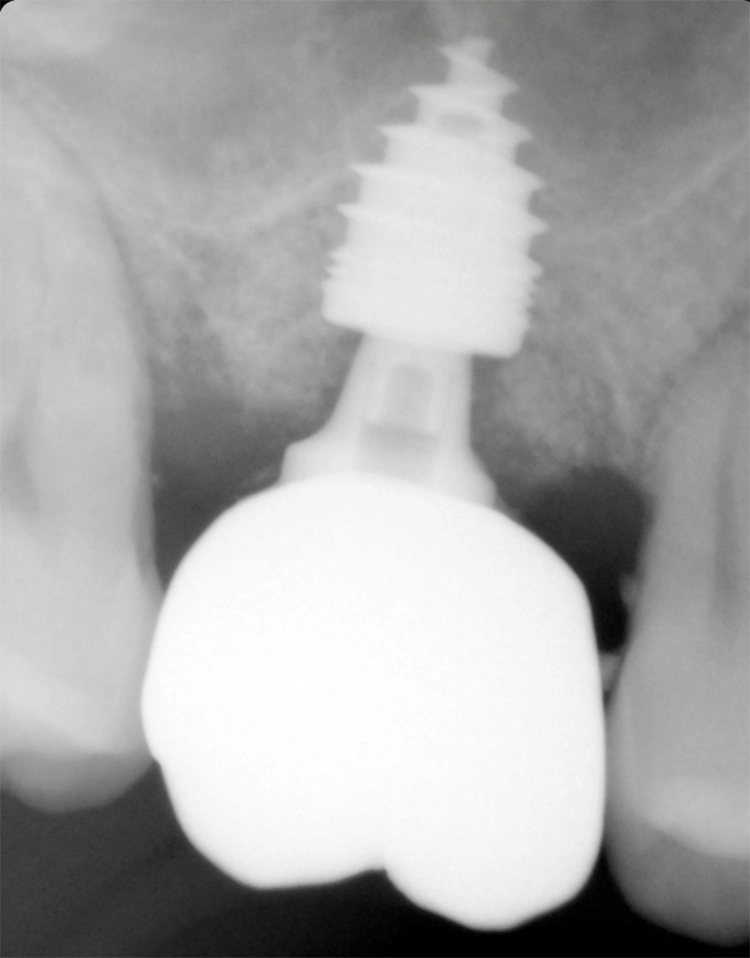

Zahn 17 konnte nicht erhalten werden. Gebohrt und mit WS-Condensern wurde im „gesunden“ Knochen im Bereich der Trikfurkation die neue Kavität zur Aufnahme eines Champions (R)Evolution L 8 mm | ø 4,0 mm mit einer finalen Primärstabilität von 40 Ncm aufbereitet (Abb. 27-29).

Dr. Nedjat

Smart Grinder-Material zum Erhalt des Emergence Profils wurde um den PEEK Gingiva Clix (der auf den Shuttle geklippt wird) mit leichtem Druck in die Restalveole eingebracht. 10 Wochen post OP wurde die Abformung digital durchgeführt (Abb. 30-33).